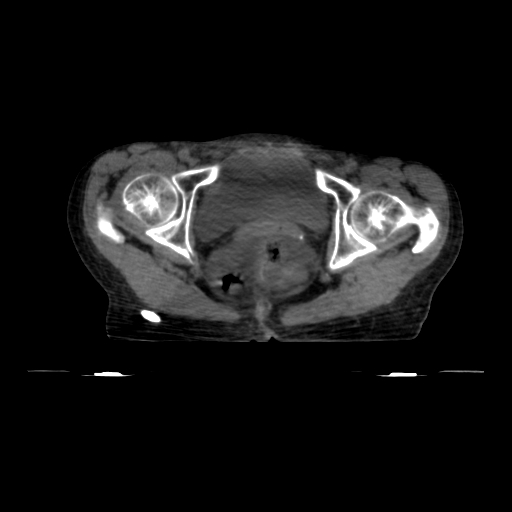

Prostate with Lymph Nodes (2 Phases with Summation)

< View All Plan Studies RADIXACT SYSTEM Prostate with Lymph Nodes (2 Phases with Summation) Case History AGE: 76-year-oldGENDER: Male Medical History Immidiate tolerance: Grade II dermatitis with eyelid edema, Grade I conjunctivitis resolved with Sterdex Diagnosis: Squamous cell carcinoma of the right lower eyelid Planning CT Images Treatment Plan Images ClearRT® Images Treatment Planning […]